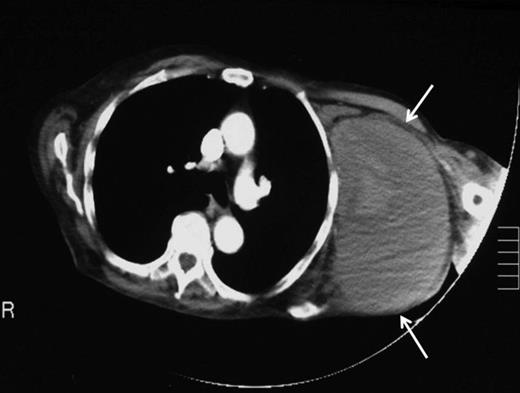

Ten weeks later a repeat orthopaedic review was requested by the rehabilitation team. There had been a slow onset and progression of oedema in the arm, with gradual progression of neurological deficit to the point at which the arm became useless and insensate. An increase in axillary bruising was noted. Also, the patient required a three-unit blood transfusion for a drop in haemoglobin six weeks after the injury. There was a thrill over the whole pectoral region and signs of venous hypertension in the arm. The left radial, ulnar and brachial pulses were normal. Repeat X ray showed subluxation of the left shoulder joint (figure 2). CT angiography revealed a distal axillary pseudoaneurysm with a sac of 15cm diameter (figure 3).

Angiographic localisation of the lesion in the third part of the axillary artery. Please note extravasation of contrast into the sac (arrows)